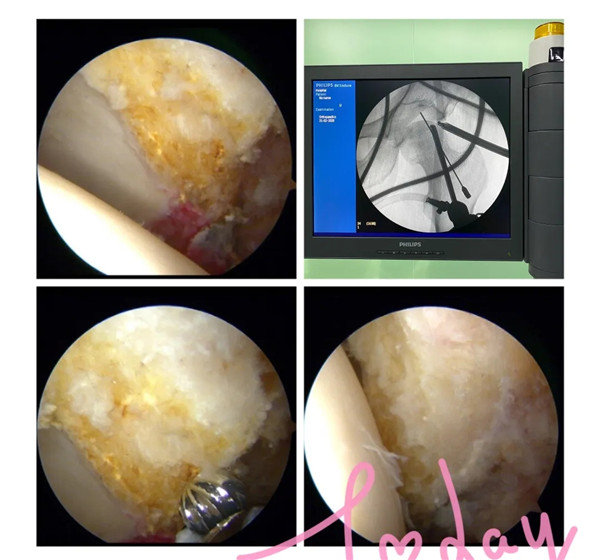

2月21日,經(jīng)過周密的術(shù)前準備,羅軍帶領(lǐng)手術(shù)團隊為余大伯開展髖關(guān)節(jié)鏡手術(shù)。術(shù)中,完成了髖關(guān)節(jié)鏡下探查清理、頭頸成形術(shù),髖關(guān)節(jié)鏡下清理術(shù),順利去除了髖關(guān)節(jié)撞擊征及盂唇破裂等病灶,并聯(lián)合運用富血小板血漿技術(shù)治療患者的股骨頭壞死。

(術(shù)中磨去增生的骨贅)

(術(shù)中去除壞死的組織并在壞死區(qū)域植入富血小板血漿)